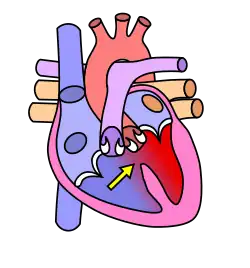

Dans le cœur normal, la cloison qui sépare les ventricules droit et gauche, dénommée « septum interventriculaire », est totalement hermétique. Une CIV correspond à la présence d'un orifice plus ou moins large dans cette cloison, permettant le passage direct du sang d'un ventricule à l'autre. Les conséquences de cette malformation dépendent essentiellement de la taille de la communication. Dans la plupart des cas, l'orifice est petit : ces CIV sans conséquence réellement gênante sont appelées « maladie de Roger ». L'évolution d'une CIV dépend de sa localisation sur le septum, certaines étant susceptibles de se fermer spontanément dans les mois ou années suivant la naissance.

Shunt droit-gauche

Le sang non oxygéné passe dans le ventricule gauche, causant une cyanose[1]

Différentes localisations des CIV

La complexité de la formation embryologique de la cloison interventriculaire, nécessitant l'alignement et la fusion de quatre constituants explique, au moins en partie, la fréquence des CIV.

Connaître non seulement la taille mais aussi la localisation d'une CIV a un double intérêt :

- certaines localisations sont parfois associées à certaines anomalies génétiques et peuvent donc inciter à pratiquer une amniocentèse pour étude du caryotype fœtal si elles sont dépistées lors des échographies anténatales.

- C'est le cas des CIV qui siègent dans le septum d'admission (partie 1 en rouge sur le schéma), fréquemment associée à une Trisomie 21, et de celles qui siègent dans le septum sous-aortique (partie 4 en bleu sur le schéma), parfois associées à une anomalie du chromosome 22 (Microdélétion 22q11) ;

- dans certaines localisations, la CIV est susceptible de diminuer de taille, voire de se fermer totalement de façon spontanée alors que dans d'autres, ce mécanisme de guérison spontané n'est jamais observé.

- les CIV siégeant dans le septum membraneux (partie 3 en jaune sur le schéma) et encore plus les CIV musculaires situées dans la partie 2 (en vert sur le schéma) sont fréquemment capables de « se guérir toutes seules » (à condition que l'état de l'enfant permette d'attendre).

- les CIV situées dans les parties 1 (septum d'admission) et 4 (septum sous-aortique) ne se ferment jamais spontanément et devront donc, sauf exception, être opérées tôt ou tard.

Schéma sur les localisations des communications interventriculaires (légende) :

- CIV membraneuse et péri-membraneuse (1-2-3)

- CIV d'admission ou postérieure (4)

- CIV musculaire ou trabéculée (5-6)

- CIV sous-aortique (7)

- CIV infundibulaire (8).

Anecdote : les CIV « infundibulaires », c'est-à-dire siégeant sous les valves pulmonaires sont fréquentes en Asie alors qu'elles sont très rares en Europe où elles pourraient être un lointain souvenir des invasions barbares. Elles ne se ferment jamais spontanément.